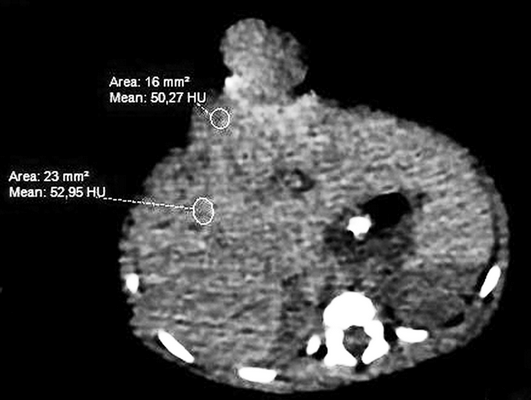

Девочке 2-х суток жизни выполнена МСКТ в условиях медикаментозной седации с проведением проспективной ЭКГ-синхронизации, болюсного внутривенного контрастирования (в/в) препаратом Визипак 270 в объеме 6 мл в периферическую вену правой нижней конечности. Сканирование осуществлено на аппарате Philips Ingenity 128, kv 80, mas 350, протяженность сканирования 250 мм. Выполнено обзорное сканирование грудной клетки и брюшной полости до контрастного усиления, по результатам которого определяется диффузная неравномерность пневматизации легочной паренхимы, с наличием участков ателектазированной легочной ткани в верхних и нижних долях легких с обеих сторон, в обеих плевральных полостях определяется умеренное количество выпота (рис. 3). Сердце визуализировано вне грудной полости (рис. 4). В грыжевом мешке определяется фрагмент паренхиматозного органа брюшной полости, по нативным денситометрических показателям идентичный паренхиме печени (50HU), как показано на рисунке 5.

Рис. 5. МСКТ брюшной полости, аксиальная проекция, визуализирован грыжевой мешок, содержащий правую долю печени